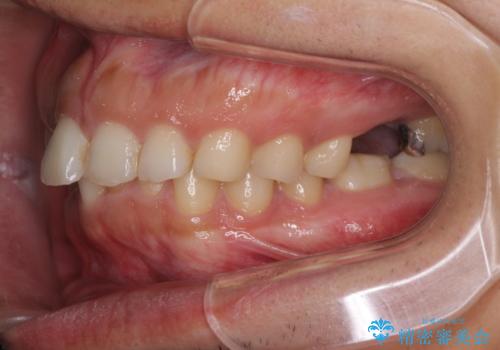

矯正治療とインプラント治療を同じ歯科医師が担当することで、通常見られるような複数医院を行き来する煩雑さや、複数担当医の見解の違いによる治療の遅滞といった煩わしさは一切なく、スムーズに治療を進めることができました。

安定して咬めるようになり、患者様には大変満足していただきました。